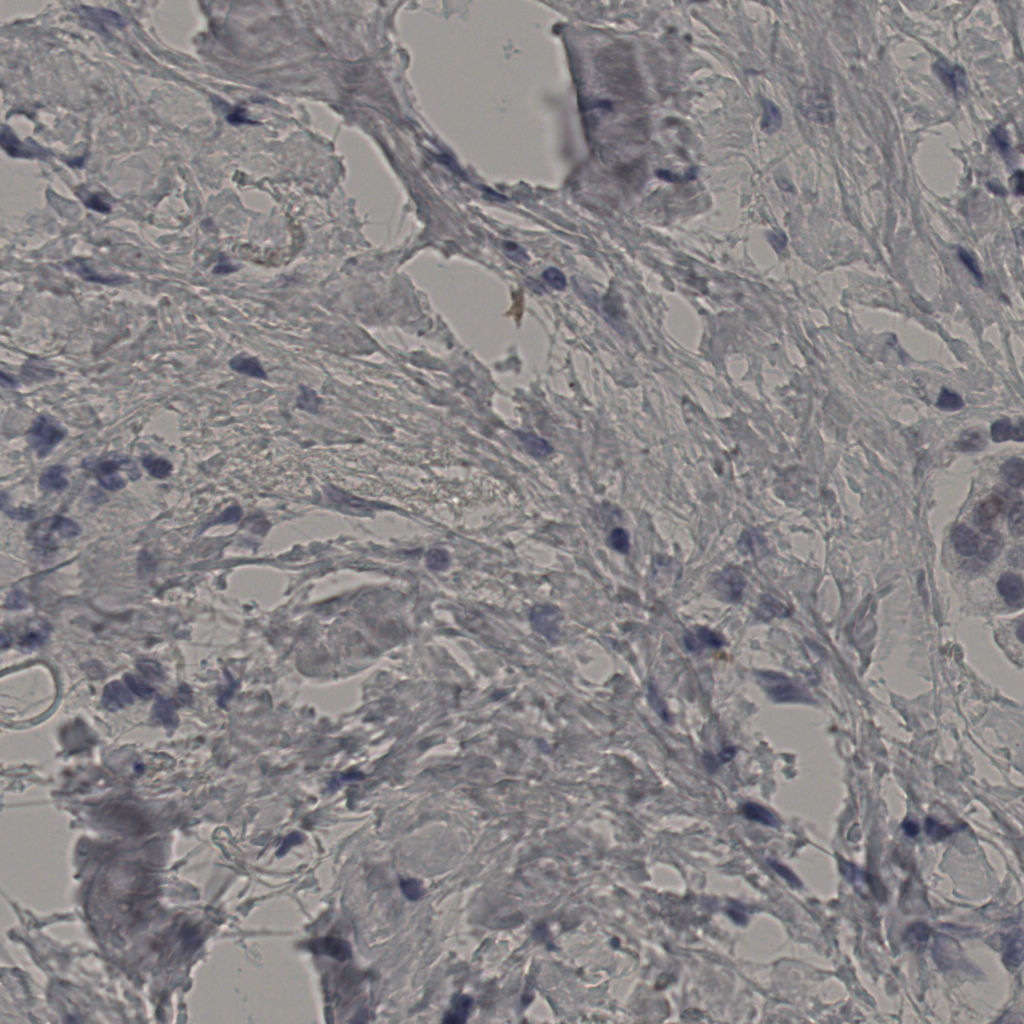

slice_43_27_x38528_y24192.png

slice_43_27_x3852...